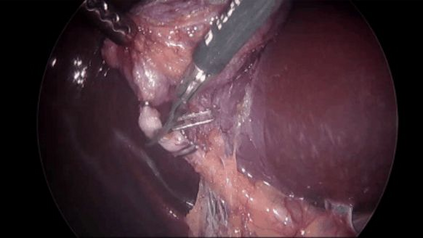

Large Vision-Language Models offer a new paradigm for AI-driven image understanding, enabling models to perform tasks without task-specific training. This flexibility holds particular promise across medicine, where expert-annotated data is scarce. Yet, VLMs' practical utility in intervention-focused domains--especially surgery, where decision-making is subjective and clinical scenarios are variable--remains uncertain. Here, we present a comprehensive analysis of 11 state-of-the-art VLMs across 17 key visual understanding tasks in surgical AI--from anatomy recognition to skill assessment--using 13 datasets spanning laparoscopic, robotic, and open procedures. In our experiments, VLMs demonstrate promising generalizability, at times outperforming supervised models when deployed outside their training setting. In-context learning, incorporating examples during testing, boosted performance up to three-fold, suggesting adaptability as a key strength. Still, tasks requiring spatial or temporal reasoning remained difficult. Beyond surgery, our findings offer insights into VLMs' potential for tackling complex and dynamic scenarios in clinical and broader real-world applications.